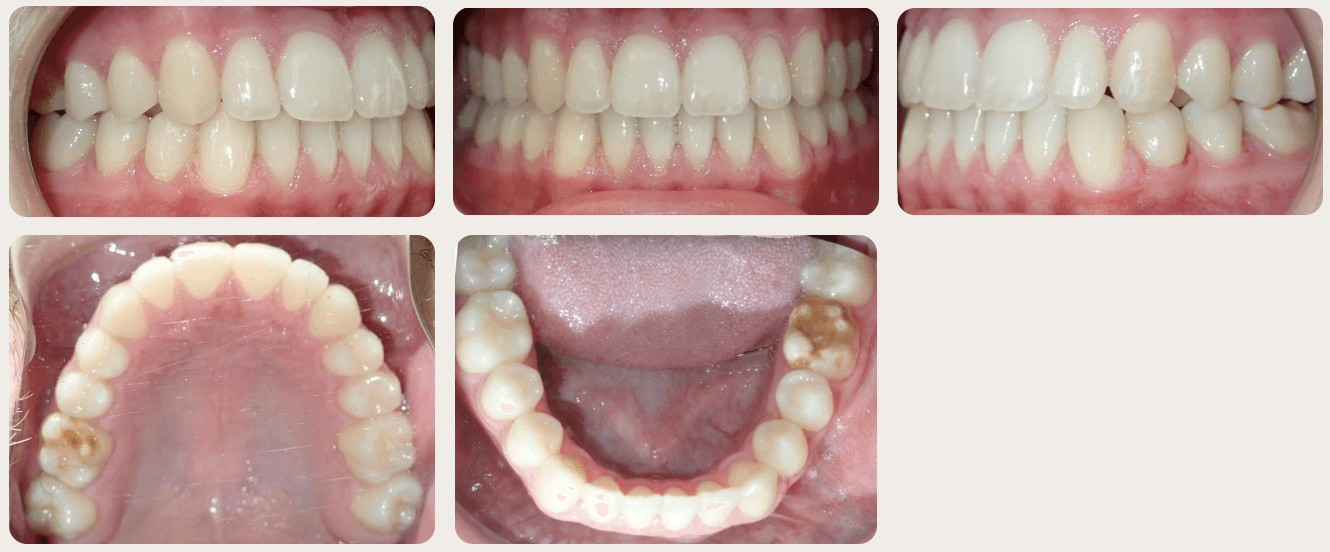

Final results

INTRAORAL